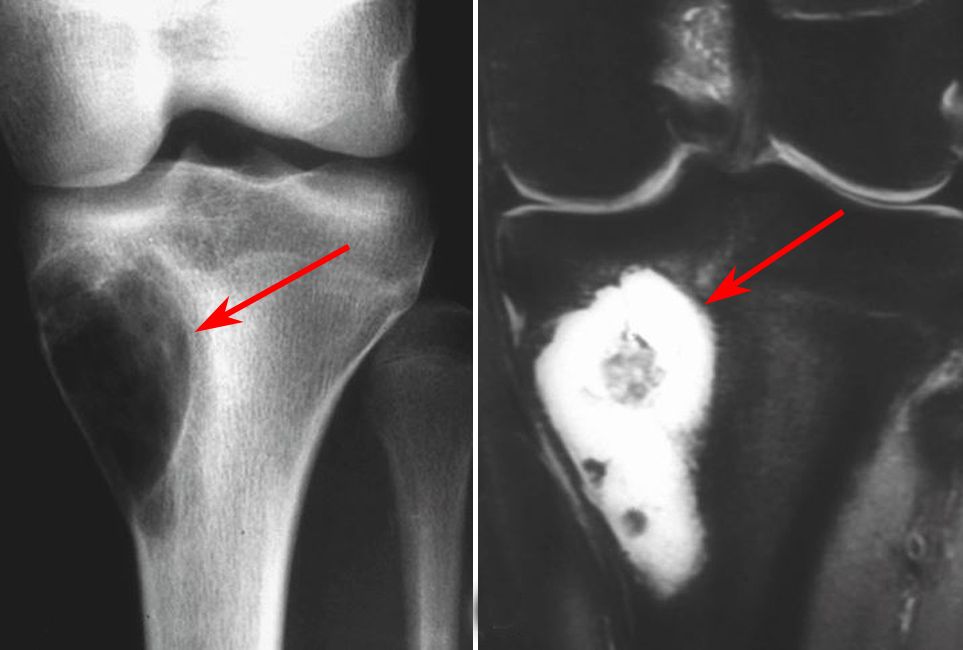

Imaging characteristics of primary osteosarcoma:

Epidemiology, pathogenesis, clinical presentation, diagnosis, and histology. Parosteal osteosarcoma is a sarcoma that has its origin on the surface of the bone. Osteosarcoma is a type of bone cancer that begins in the cells that form bones. Osteosarcoma is a malignant tumor that primarily affects the long bones but can also involve other bones this chapter will highlight the clinical presentation, diagnosis, and treatment of osteosarcoma. It starts in immature bone cells that normally form new bone tissue destroys tissue, weakening the bone. An osteosarcoma (os) or osteogenic sarcoma (ogs) (or simply bone cancer) is a cancerous tumor in a bone. Osteosarcoma of the femur with skip, lymph node, and lung metastases. Imaging characteristics of primary osteosarcoma: A report from the childrens oncology group bone tumor committee. Bielack s, machatschek j, flege s, jürgens h: Grows primarily into the surrounding soft tissues, but may also infiltrate into the bone marrow. Osteosarcoma is the most common malignant bone tumor (if one excludes myeloma). Osteosarcoma is a cancer of the bone.

Adjuvant multiple drug chemotherapy for osteosarcoma of. Bielack s, machatschek j, flege s, jürgens h: It starts in immature bone cells that normally form new bone tissue destroys tissue, weakening the bone. Imaging characteristics of primary osteosarcoma: Delaying surgery with chemotherapy for osteosarcoma of the extremities.